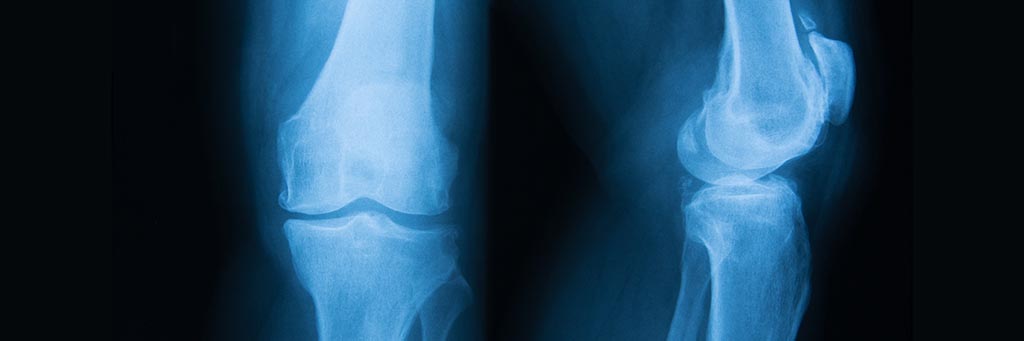

All forms of arthritis manifest themselves as stiffness, inflammation, or pain and osteoarthritis refers to the deterioration of the tender joint cartilage that connects the different parts of our bodies to the underlying bone (“osteo” is Greek for “bone”). It is also commonly referred to as “wear and tear” arthritis as it develops slowly over time from the strains and pressures put on tender joint cartilage. Our bodies are designed to flex at certain key joints, that include: the hand, wrist, knee, neck, back, and hip. Anywhere you can swivel or pivot is a joint, and may be susceptible to osteoarthritis.

Bone spurs – Over time, tiny hard nodules or bumps may form on the bone around an affected joint